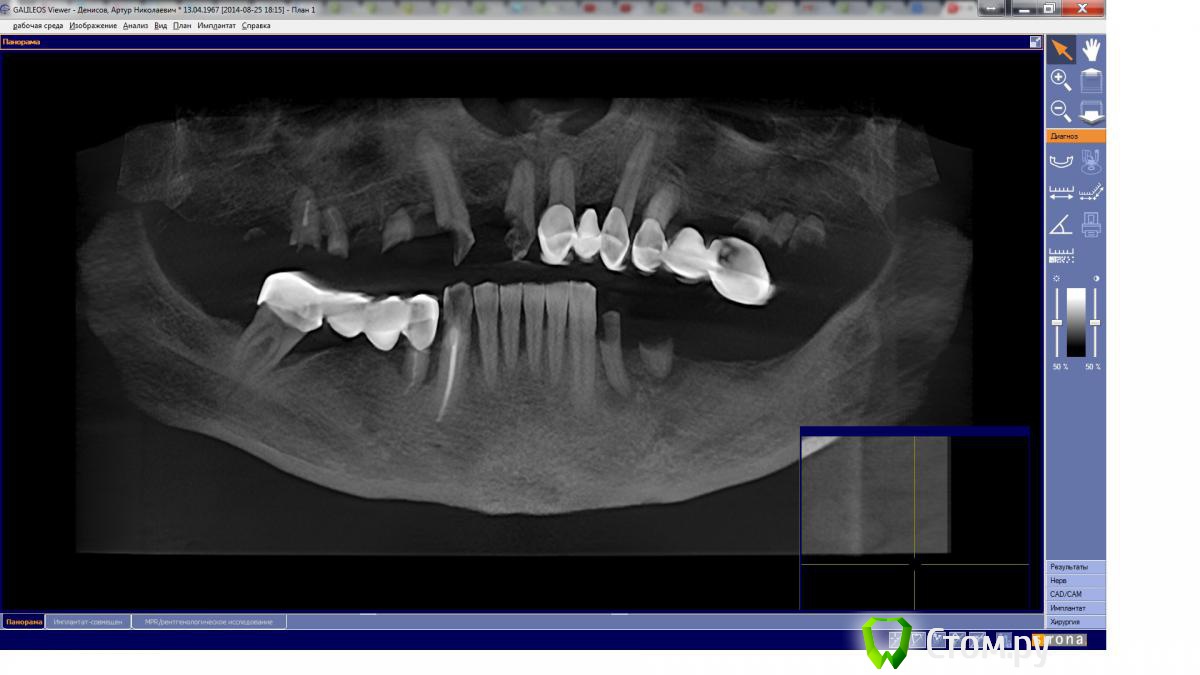

13Art31 Опубликовано 28 августа, 2014 Поделиться Опубликовано 28 августа, 2014 Здравствуйте! Огромная просьба специалистов дать совет как лучше поступить дальше. Пока про верх (низ оставим на потом).11,13 и 14 были под мостом,мост пал.11- гранулема и сам зуб не очень 13 – корень вроде ничего, верх разрушен но вроде не сильно14 - разрушен удалениеУ 11 и 13 чувствуется небольшая подвижность (в одном месте их лечить отказались, в другом вроде берутся вылечить + штифт)21 и 23 под мостом, состояние не понятно корни вроде ничего, подвижность если и есть то минимальная. 24 – сказали удаление (под ним кажется эрозия кости)+ Куча корней Мене 46, не курю, бюджет около 200 тыс руб, ну может 300.Вопрос что делать дальше: 1) лечить11 и 13, делать 2 передних моста и придумывать что-то с жевательными?На долго ли хватит этих передних мостов?Что делать с жевательными? Съемное очень не хочется, там можно что-то на имплантатах? И сколько их будет нужно? 2) Удалить ВСЕ и делать что-то не съёмное , типа All-on-4 (можно ли это сделать в моем случае?). Нужно время на вживление, как питаться (улыбаться), делать временный съемный? Или возможно сразу временный несъёмный? Что еще можно придумать несъемное с моим бюджетом? Базальная, я так понял, здесь не приветствуется (а как хорошо расказывают и картинки рисуют). Балочный протез на имплантах, мини-имплантация (MDI) - сильно ущербные варианты? Нахожусь в прострации, очень буду благодарен за ценные советы, живу в Липецке 450 км от Москвы, доехать не проблема, могу стать потенциальным клиентом. КТ (GALILEOS Sirona) 300 мбhttps://drive.google.com/folderview?id=0B9z3eSTiYecyc2hwbVIwcklVQVE&usp=sharing Ссылка на комментарий

faity Опубликовано 28 августа, 2014 Поделиться Опубликовано 28 августа, 2014 Артур Николаевич, на верхней челюсти 2 зуба остается- 1.3 и 2.3на нижней 3 зуба- 3.3, 3.2, 4.3вопрос- что ортопеды скажут. 1 Ссылка на комментарий

Mane Опубликовано 29 августа, 2014 Поделиться Опубликовано 29 августа, 2014 на верхней нет смысла что то спасать если курс взят на имплантациювнизу с клыка по клык все остается Ссылка на комментарий

Doc Опубликовано 29 августа, 2014 Поделиться Опубликовано 29 августа, 2014 на верхней нет смысла что то спасать если курс взят на имплантациювнизу с клыка по клык все остаетсяПолностью согласен, но 41-42 тоже под большим вопросом, хоть и не шатаются пока, скорее всего. 1 Ссылка на комментарий

faity Опубликовано 29 августа, 2014 Поделиться Опубликовано 29 августа, 2014 Полностью согласен, но 41-42 тоже под большим вопросом, хоть и не шатаются пока, скорее всего.на 3.1 костный кратер же на 2/3 корня, или мне видится? Ссылка на комментарий

Doc Опубликовано 29 августа, 2014 Поделиться Опубликовано 29 августа, 2014 на 3.1 костный кратер же на 2/3 корня, или мне видится?Так это от 4.1, у 3.1 хоть с одной стороны кость есть! Ссылка на комментарий

Sahan Опубликовано 30 августа, 2014 Поделиться Опубликовано 30 августа, 2014 Так это от 4.1, у 3.1 хоть с одной стороны кость есть!Если будет планироваться имплантация в обл 4.1;4.2- то из за оголения корня 3.1 на 2/3 со стороны 4.1, логично удалить 3.1 и установить имплантаты в позиции 3.1 и 4.2. Ссылка на комментарий

Doc Опубликовано 30 августа, 2014 Поделиться Опубликовано 30 августа, 2014 Если будет планироваться имплантация в обл 4.1;4.2- то из за оголения корня 3.1 на 2/3 со стороны 4.1, логично удалить 3.1 и установить имплантаты в позиции 3.1 и 4.2.Да боюсь, что если удалять 4.1 и 4.2, то они за собой потянут и 4.3! А тогда оставлять 2-3 зуба слева уже и смысла не будет. Либо центр весь оставлять на развод, либо уж сносить все и делать всена4, чтобы минимализировать затраты. Оба варианта не идеальные, а куда деваться? Ни одного идеального тут нет. Ссылка на комментарий